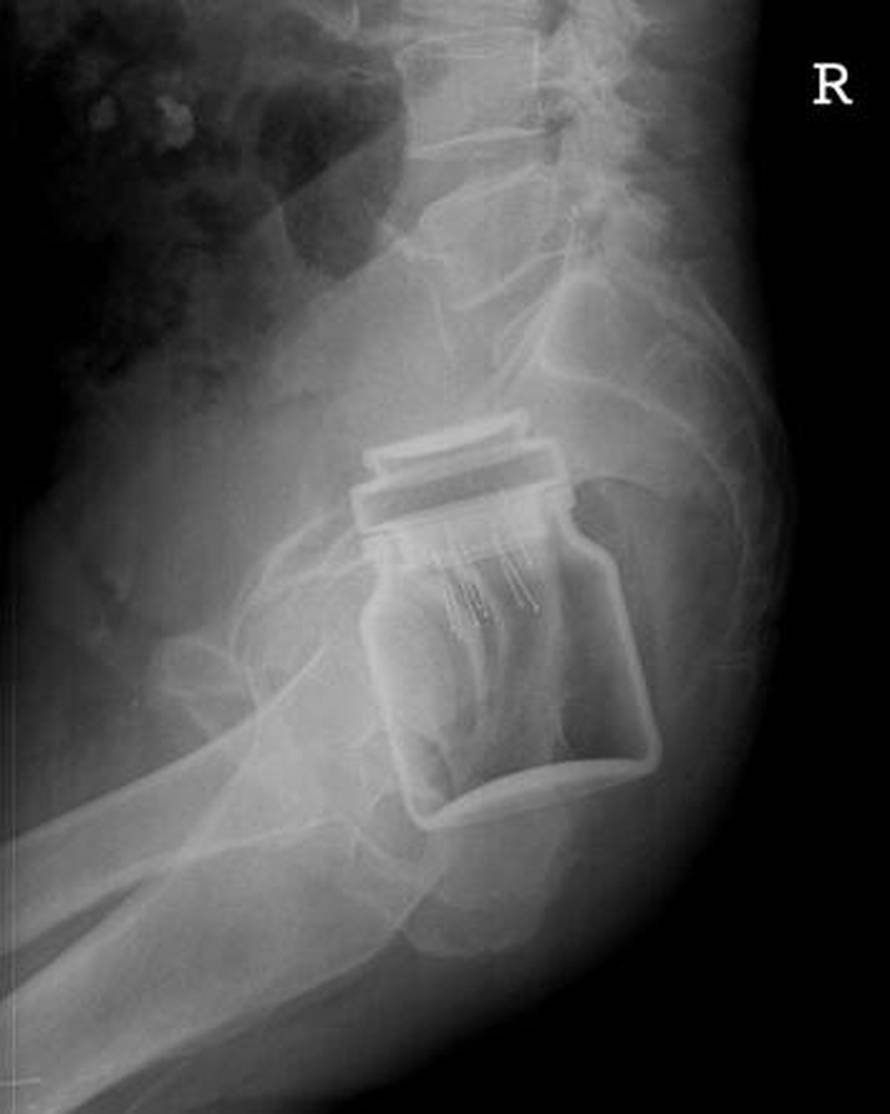

BIZARNE IGRICE: Kirurzi Kliničke bolnice Merkur u Zagrebu iz anusa maštovitih pacijenata moraju vaditi predmete koji 'pobjegnu' tijekom 'igrica'